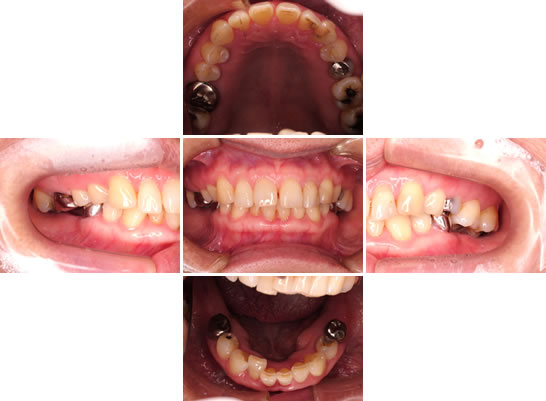

インプラント症例その1

| 年齢・性別 | 59歳・女性 |

| 主訴 | 左下詰め物取れた |

| 問題点 | 下顎臼歯部の咬合が欠如しているため、上顎の臼歯部が提出(下に延びてしまっている)。またそのため常に前歯で噛むため、前歯が押し出され「隙きっ歯」になってしまっています。 |

| 治療方法 | 下顎臼歯部に歯を入れる為に上顎臼歯部の治療を行い、全体的な噛み合わせの治療を行う。 |

外科処置

下顎臼歯部にインプラント処置を行い、インプラントの上部構造(差し歯)を入れるスペースを作る為、上顎臼歯部の虫歯・神経の処置を行い歯肉の外科処置を行いました。写真は左側ですが、右側も同様の処置を行いました。